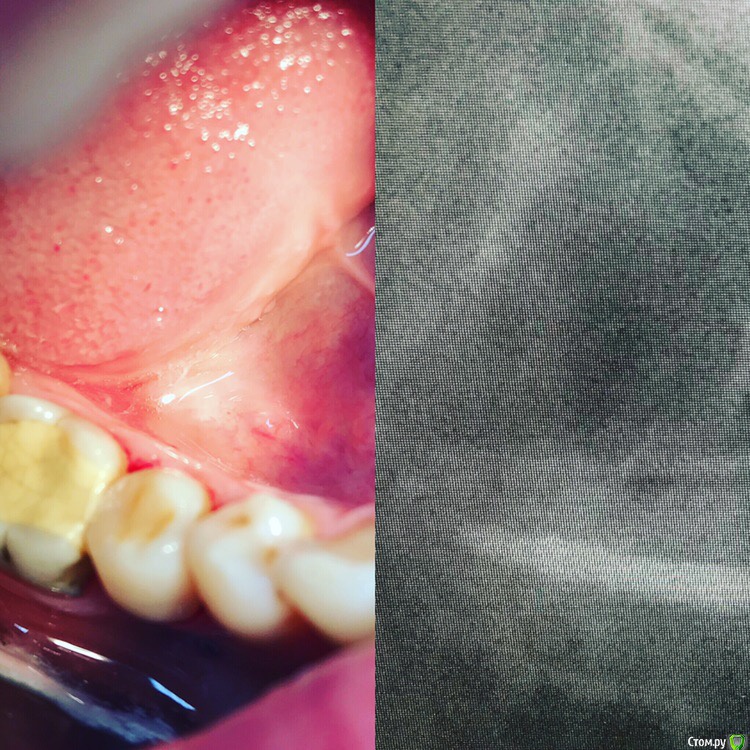

1586Doc Опубликовано 30 марта, 2019 Автор Поделиться Опубликовано 30 марта, 2019 (изменено) Еще немного работы45 зуб эндо и пломба и 46 зуб эндо и пломба на снимке справа Изменено 30 марта, 2019 пользователем 1586Doc Ссылка на комментарий